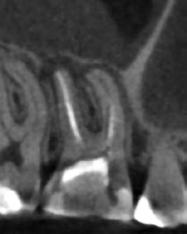

1. ábra: A 15-ös foggyökér meziális felszíne mellett látható radiolucens elváltozás, illetve a felvételen látható a korábban behelyezett gyökértömés, a parapulpális csap segítségével elhorgonyzott csonkfelépítés és a fogat borító cirkonkorona. –2. ábra: A saggitalis irányú CBCT-metszeten jól megfigyelhető az állcsontgerincet elérő radiolucens elváltozás. – 3. ábra: Az axiális irányú CBCT-metszeten egyértelműen látható a kezeletlen palatinális gyökércsatorna, valamint a radiolucens elváltozás mezio-disztális kiterjedése is jól megítélhető. – 4. ábra: A palatinális gyökércsatorna szelektív endodonciai kezelése során először gyógyszeres zárás került behelyezésre. – 5. ábra: A gyógyszeres zárás során alkalmazott kalcium-hidroxid alapú paszta a szulkuszon keresztül a szájüregbe extrudálódott. – 6. ábra: A gyökértömő anyag a középső és apikális gyökéri harmad határán lévő laterális csatornán keresztül a periapikális térbe extrudálódott. 7. ábra: A kezelések befejezését követően 4 évvel készült röntgenfelvételen jól látható a csontállomány gyógyulása és a fiziológiás gyökérhártyarés újbóli kialakulása. –8. ábra: A peroperatív CBCT-felvétel alapján készített koronális irányú metszeten jól látható a gyökércsúcs körül lévő periapikális felritkulás. – 9. ábra: A kezelések befejezése után 4 évvel készített CBCT-felvételen a gyulladásos lézió teljes megszűnése észlelhető.

10. ábra: A periapikális felvételen egyértelműen megmutatkozik a 46-os és 47-es fogak között kialakult csontos defektus, valamint a gyökereket fedő parodontális rostok károsodása. – 11. ábra: A disztális gyökér amputációját követően a csonthiány kiterjedése látszólag tovább növekedett. – 12. ábra: A 22 évvel később készített kontrollfelvételen jól megfigyelhető a csontos defektus telődése, valamint új kortikális csontállomány kialakulása.